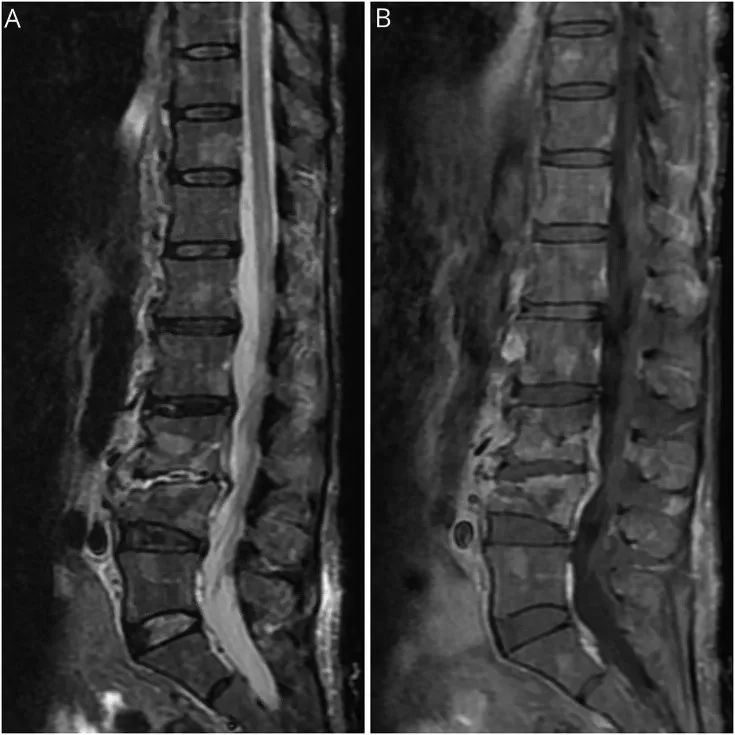

脊柱MRI(图)显示退行性变,受累椎体有MM,L3-L4压缩性骨折,但未显示出脊髓信号改变或受压,也未见马尾神经增强。值得关注的是,包括脊椎管和椎间孔狭窄在内的脊椎退行性变不能解释患者的神经功能障碍或EMG / NCS显示的去神经病变的程度。因此,神经影像学排除了弥漫性神经根受累的机械性病因。

图 脊柱MRI。短T1反转回复序列(STIR)矢状位(A)和T1增强矢状位(B)显示整个脊柱多个增强性、STIR高信号病灶,L3和L4椎体的病理性压缩性骨折,符合脊柱多发性骨髓瘤。此外,还可见弥漫性退行性改变,表现为多个水平的椎管和椎间孔狭窄。无脊髓信号异常或受压的表现。